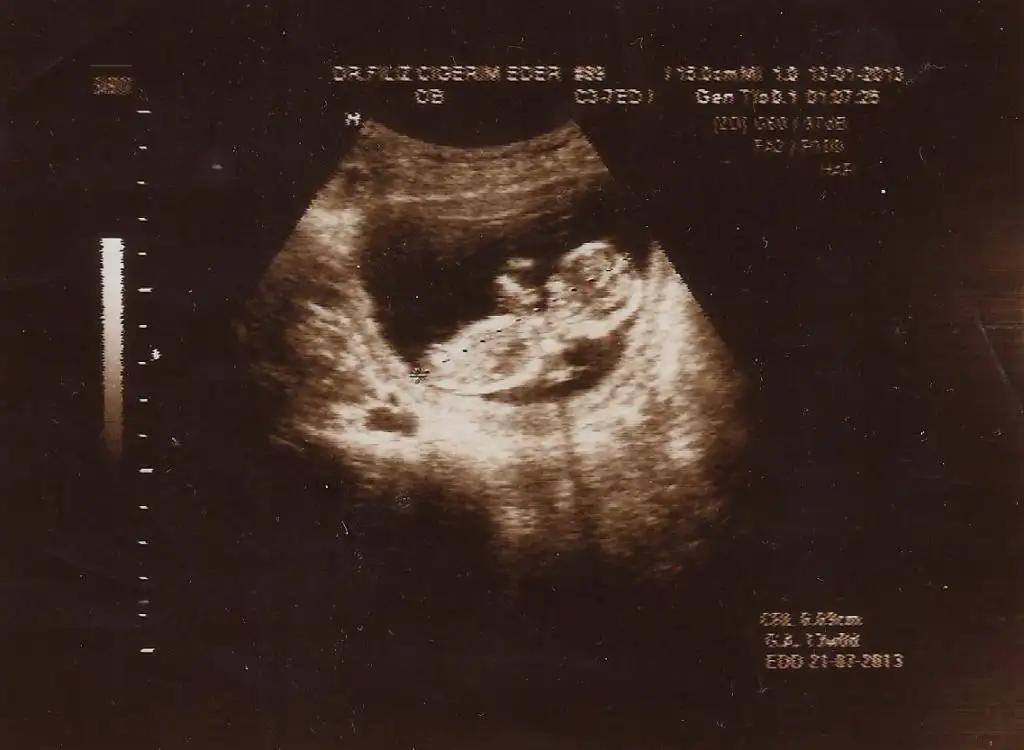

dr soylemeden siz gorun genital nub teorisi ( bebegin cinsiyeti)

teyzeleri benim bebsim burda 13 haftalik bizde yorumlarinizi alabilirmiyiz daha cinsiyeti belli deyil ilk bebisim merak ediyoz simdiden tesekkurler

Slmlar .Banada bi yorum yaparmisiniz. Ben arada kaldım.. 10 hatt. Benm bebisim.